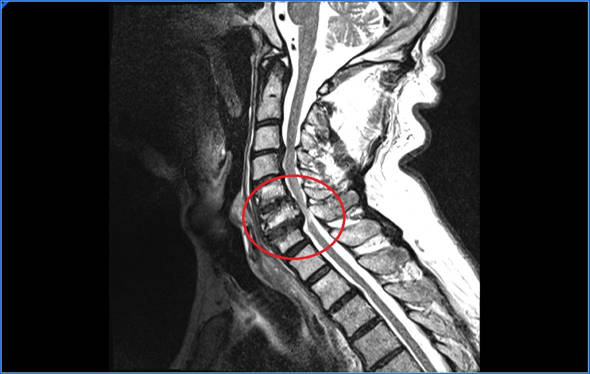

Resonancia magnética. Es la prueba que más información aporta. En la RMN veremos si efectivamente tenemos una hernia C5-C6, veremos si la hernia estrecha el agujero por el que sale la raíz nerviosa o comprime la médula espinal.

La mielopatía ocurre cuando la hernia C5-C6 comprime la médula espinal. La mielopatía cervical tiene síntomas motores, sensitivos, alteración de esfínteres, alteración de reflejos e inestabilidad a la marcha. La dificultad para diagnosticar una mielopatía cervical estriba en que los síntomas son muy variables, tanto en las zonas del cuerpo que se ven afectadas, como en la gravedad de los síntomas.